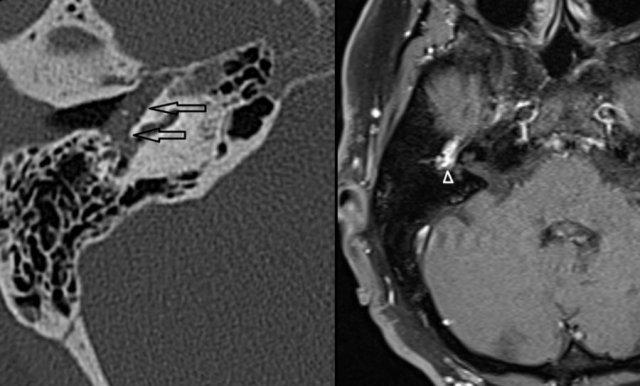

Xơ cứng tai: xương giảm tỷ trọng ở vùng fissula ante fenestram trong xơ cứng tai thể cửa sổ (trái). Xơ cứng tai thể ốc tai biểu hiện là một vùng hào quang giảm tỷ trọng bao quanh ốc tai trên CT (phải).

Xơ cứng tai (Otosclerosis)

Còn được gọi là xốp xương tai (otospongiosis), là một quá trình thâm nhiễm vô căn của xương đá.

Bệnh gây ra cả điếc tiếp âm và điếc dẫn truyền, và có thể là nguyên nhân gây ù tai theo nhịp mạch.

CT độ phân giải cao, lát mỏng thường cho thấy xương giảm tỷ trọng bất thường ở vùng fissula ante fenestram trong xơ cứng tai thể cửa sổ (trái).

Xơ cứng tai thể ốc tai

Biểu hiện là một vùng hào quang giảm tỷ trọng bao quanh ốc tai trên CT (phải).